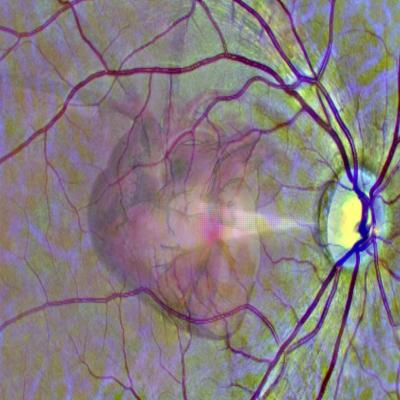

A graphic representation of the idea of using a scan of the eye to get a window into heart health. Credit: University of Leeds.

Changes to the tiny blood vessels in the retina are indicators of broader vascular disease, including problems with the heart. In the research, led by the University of Leeds, deep learning techniques were used to train an AI system to automatically read retinal scans and identify those people who, over the following year, were likely to have a heart attack. Deep learning is a complex series of algorithms that enable computers to identify patterns in data and to make predictions.